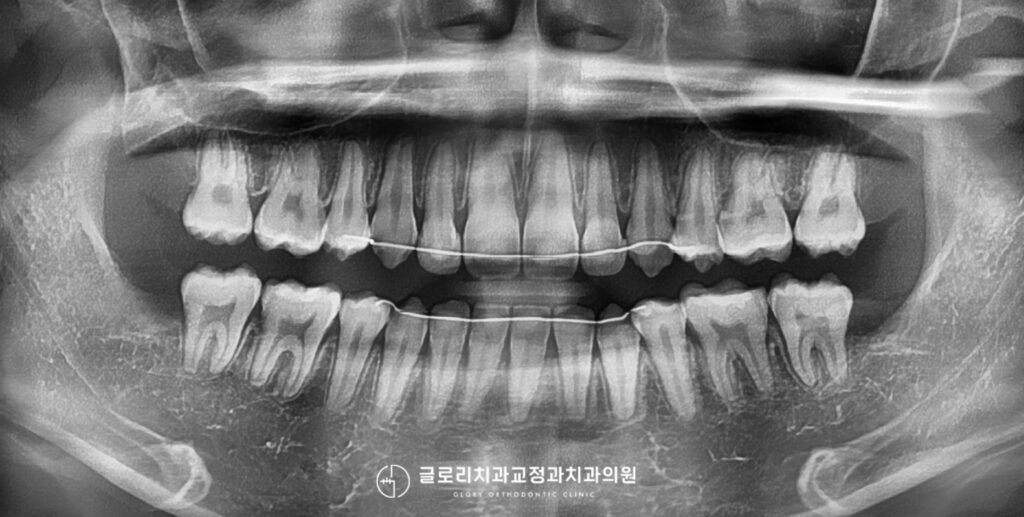

준비된 사진을 보면 현재 상악 전치부 사이가 벌어져있으며, 전반적으로 전방으로 뻗어 있는 양상을 보이고 있습니다.

또한 우측 측절치는 인접치에 비해 크기가 작은 왜소치 형태를 띠고 있어 자연치 비율의 불균형이 더욱 두드러져 보이죠.

측면에서 보면 과도한 수평피개로 인해 전치부 돌출양상이 더욱 도드라져 보입니다.

수평피개란 쉽게 말해 위앞니가 아래에 비해 얼마나 앞으로 나와있는지를 의미하는데, 이 수치가 과도하게 증가하면

안모사진을 보면 상순이 전방으로 위치하고있는데 골격성 2급부정교합의 한 형태로 전치부의 전방경사와 과도한 수평피개가

함께 작용한 결과라 볼 수 있습니다. 이때 도입될 수 있는 것이 발치교정인데 위아래 4개의 치아를 제거한 후 확보된 공간을 이용해